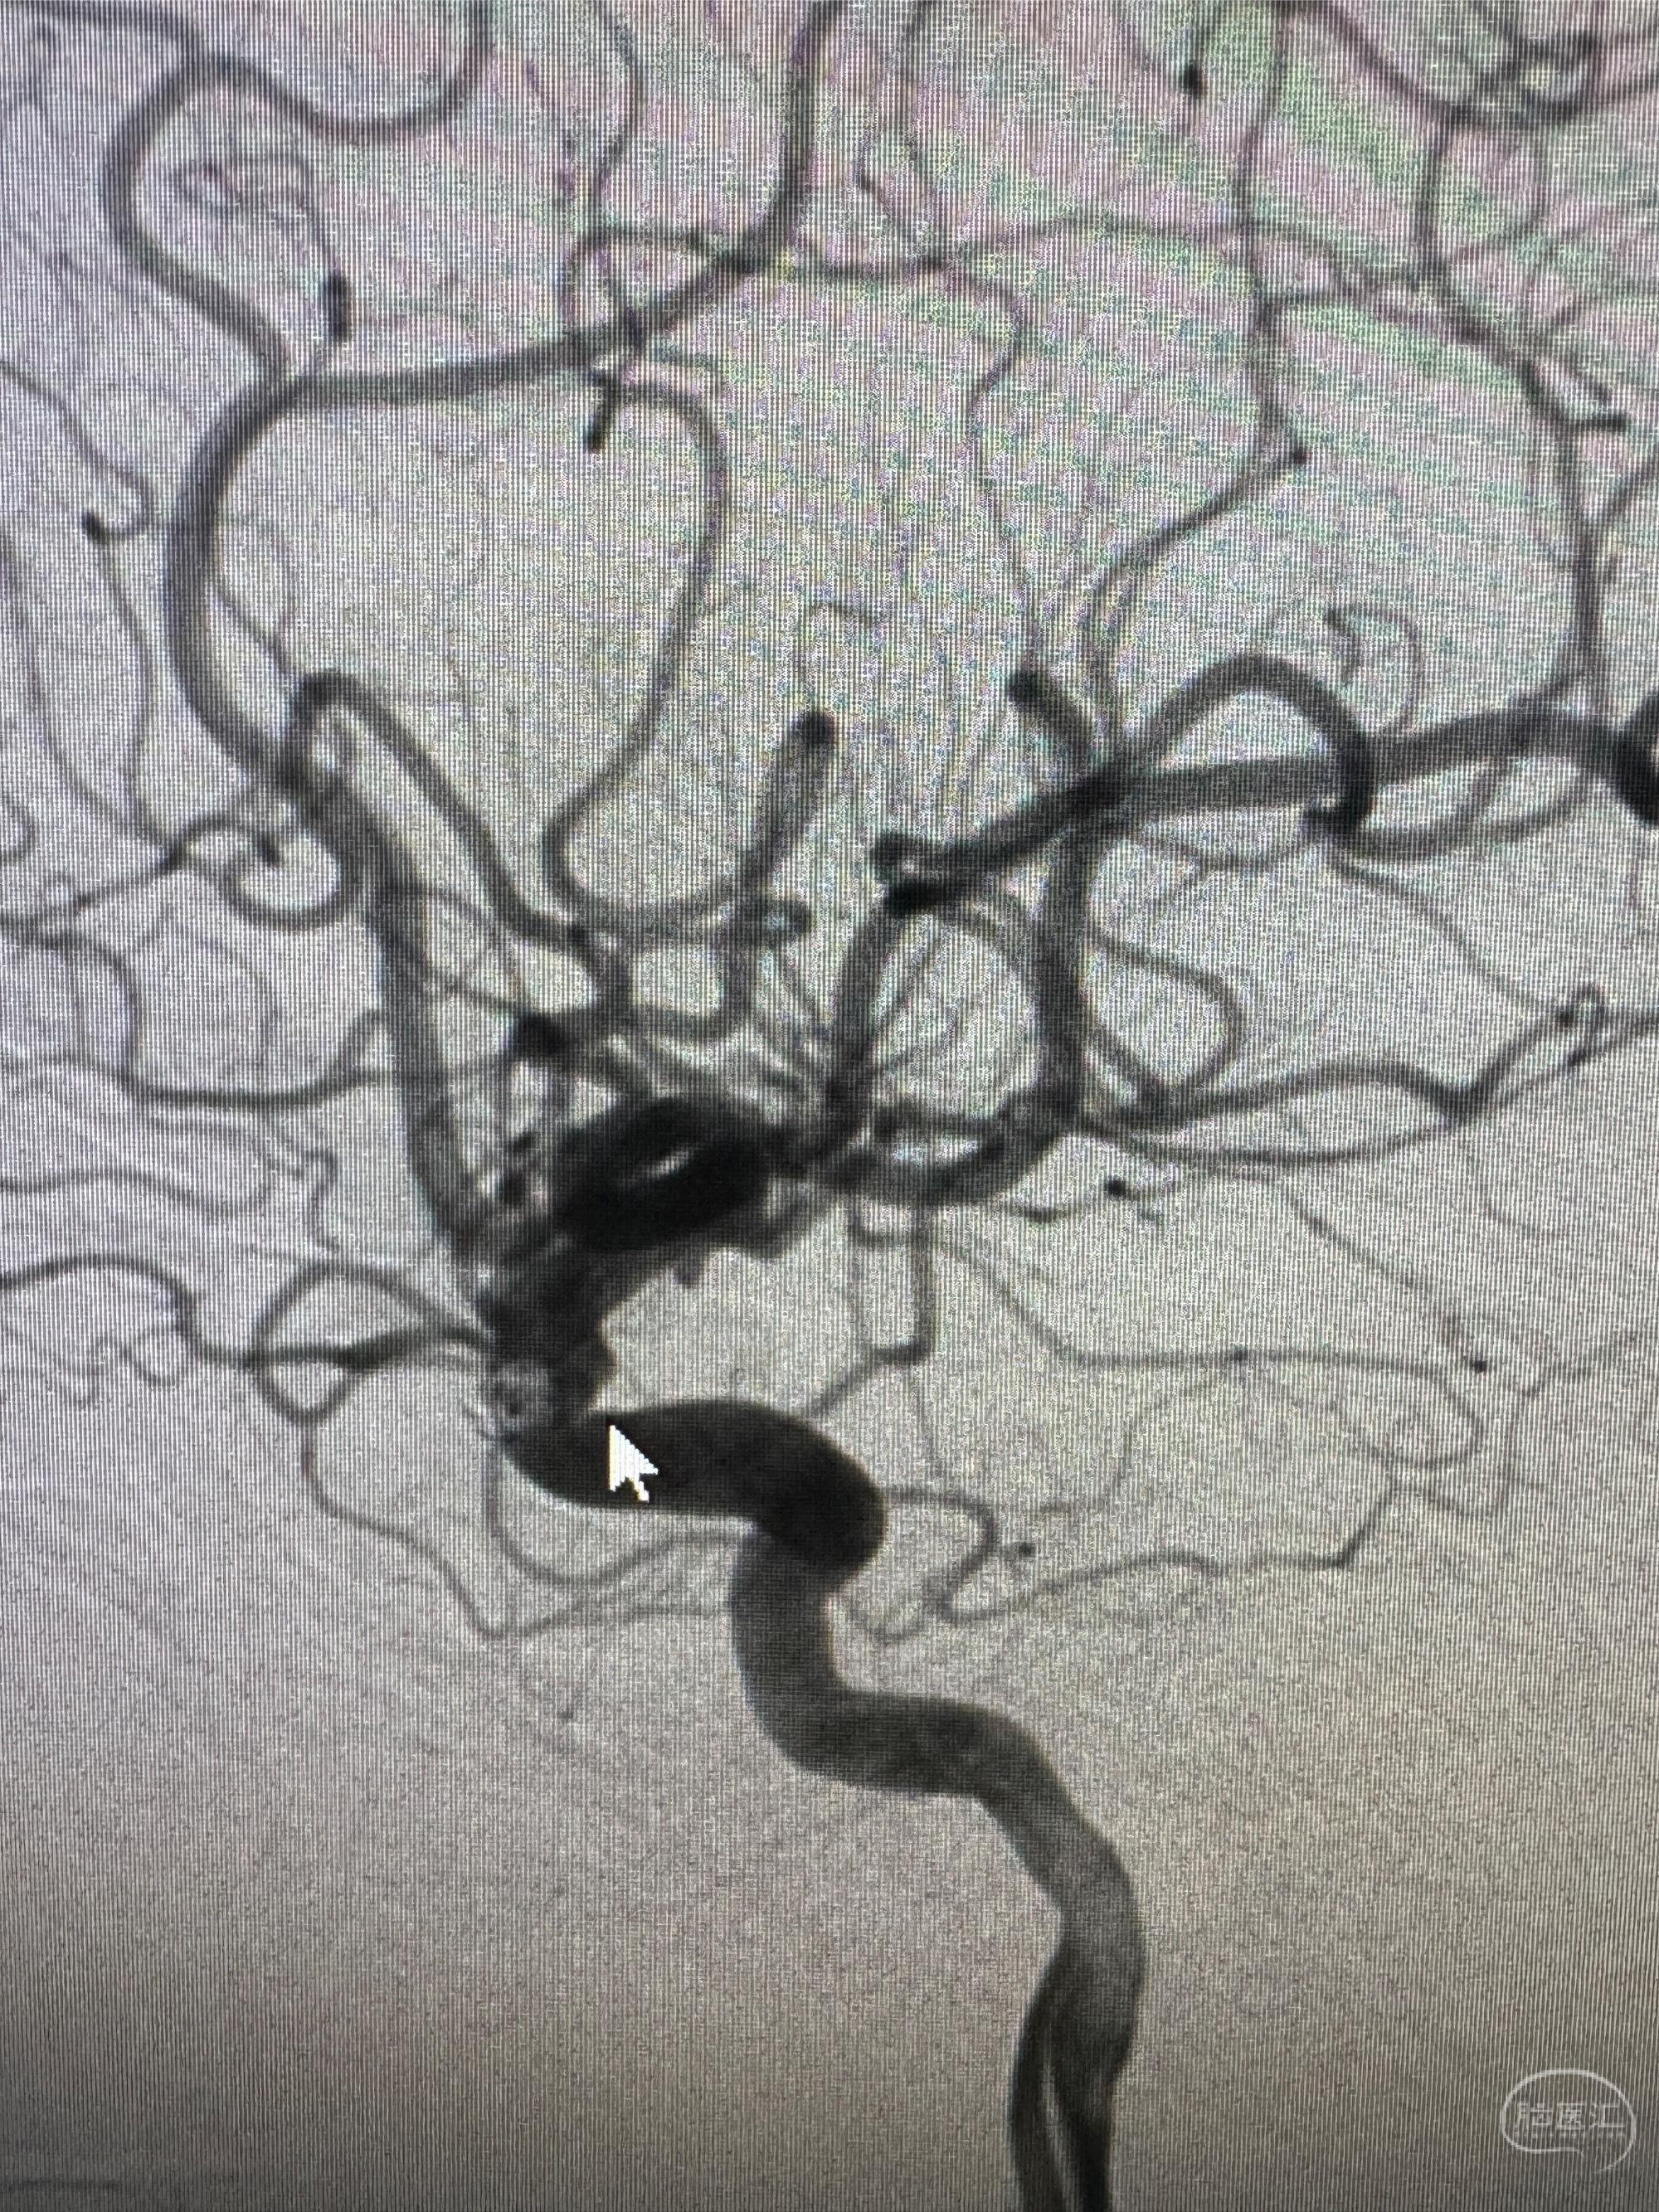

2023.12.26术后6月复查DSA:动脉瘤痊愈,局部不规则动脉膨出与前相仿

6个月复查显示密网支架内内膜增生,局段不规则动脉膨隆于术后即刻相仿,给予强化降脂:立普妥+依折麦布,6月后再随访